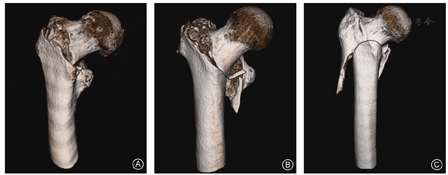

目前,股骨转子间骨折临床常用分型是Evans分型[9]、Evans-Jensen分型[10]和AO/OTA分型[11]。Evans分型创建于1949年,以转子间骨折的稳定性和骨折线走行方向为依据分为两型(图3)。EvansⅠ型的骨折线由小转子向上、向外延伸,共4个亚型,即Ⅰa型:骨折无移位的稳定型骨折;Ⅰb型:骨折部分移位,伴小转子骨折;Ⅰc型:骨折移位,小转子游离,经复位后内侧皮质无法附着,骨折不稳定;Ⅰd型:粉碎性骨折,骨折至少呈四部分,大、小转子为单独骨块,骨折不稳定。EvansⅡ型为反转子间斜形骨折,骨折线由小转子向外下方走行,骨折不稳定,该类骨折因内收肌群的牵拉,股骨干易向内侧移位;反斜型骨折发生率较低,且常伴转子下骨折。Evans分型中,Ⅰa、Ⅰb型为稳定型骨折,其余为不稳定型骨折。1975年,丹麦学者Jensen等对Evans分型进行了改良,将股骨转子间骨折分为5型,称为Evans-Jensen分型,即Ⅰ型:无移位的两部分骨折;Ⅱ型:两部分骨折伴移位;Ⅲ型:三部分骨折,骨折块累及大转子;Ⅳ型:三部分骨折,骨折块累及小转子,缺乏内侧支持;Ⅴ型:四部分骨折,骨折累及大、小转子,缺乏内、外侧支撑。AO/OTA分型既对股骨转子间骨折形态学进行了描述,又对骨折的预后作出了判断,且在内固定物的选择方面也具有一定的指导意义[11]。AO/OTA分型将转子间骨折分为3型(图4),每型又根据骨折线的走行和粉碎程度被分为3个亚型。其中,31-A1型为简单的两部分骨折,具有良好的内侧皮质支撑;31-A2型为经转子的粉碎性骨折,内侧和背侧骨皮质在多个平面上断裂;31-A3型为外侧皮质断裂的反转子间骨折。需要说明的是,目前尚无单一的股骨转子间骨折分型金标准,现有的分类系统均无法涵盖所有的创伤类型。